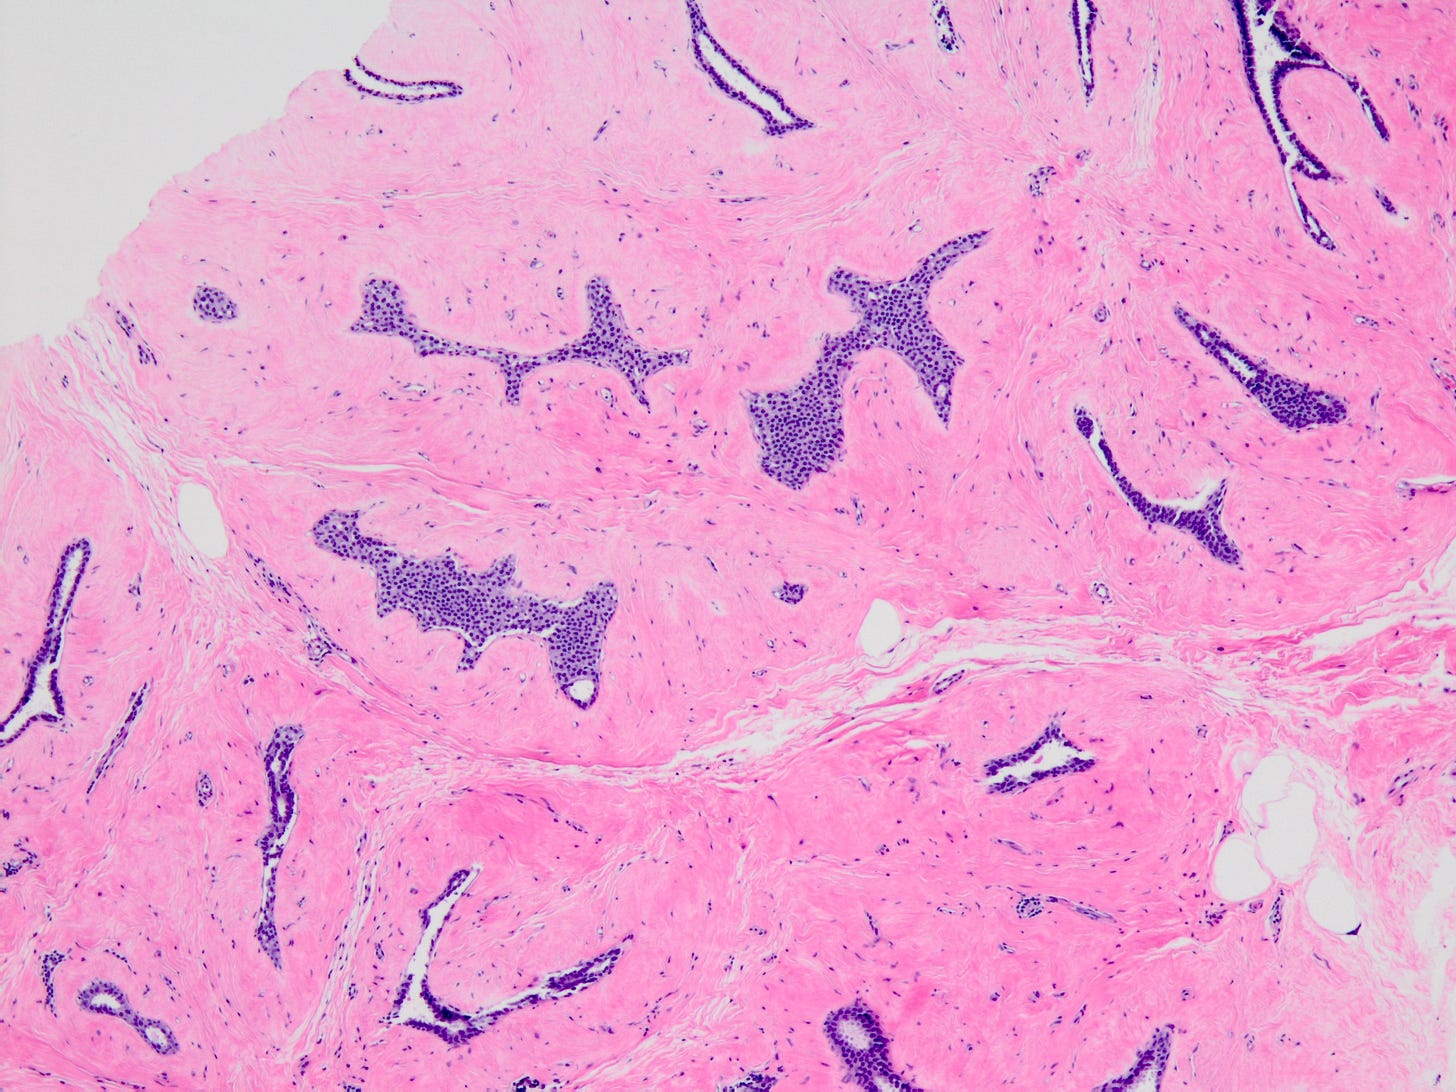

Lobular carcinoma in situ (LCIS) - classic is a precursor of infiltrating duct carcinoma of no special type (IDC), invasive lobular carcinoma-classic and pleomorphic lobular carcinoma. LCIS has two nonclassic variants - LCIS florid and LCIS pleomorphic, that are not precursors of IDC but will be discussed below under lobular carcinoma.

Normal breast cells appear to transform to LCIS based on changes to the E-cadherin gene (mutations, loss of the wild type allele or methylation). E-cadherin mediates intracellular adhesion and cell polarity and plays a key role in maintaining lobular architecture; it can also inhibit the growth and invasion of breast cancer cells. Loss of E-cadherin protein (which occurs in > 95% of cases), or rarely its aberrant expression (due to mutations or loss of the wild type allele), results in loss of cell to cell cohesion, increased cell proliferation and altered organization of the lobules, giving rise to the characteristic microscopic appearance of lobular carcinoma in situ.

As shown below, LCIS is characterized by a lobulocentric proliferation of cells that expand lobular units. The LCIS cells are uniform, loosely cohesive and evenly spaced (“marbles in a bag”). They are slightly larger than normal breast epithelial cells, with indistinct cell borders and pale cytoplasm. Two types may coexist. Type A LCIS cells have small to slightly enlarged, uniform, round nuclei with inconspicuous nucleoli. Type B cells have larger nuclei, more abundant cytoplasm and more prominent nucleoli.

Classic LCIS is usually an incidental finding in a breast biopsy performed for other indications, including screening detected calcifications or mass producing lesions. The calcifications are frequently produced by columnar cell lesions, a low risk lesion. LCIS lesions are frequently found as multiple foci within the same (70%) or both breasts (20 - 60%).

LCIS is a risk factor for subsequent breast cancer: women with LCIS have a 7 - 10 fold increase in breast cancer risk, an absolute risk of 1 - 2% per year and a lifetime risk of 30 - 40%. The time from LCIS diagnosis to cancer ranges from 15 to 30 years.

Classic LCIS is typically treated conservatively with active surveillance and anti estrogens. Unlike DCIS, it is no longer considered a malignant condition. If diagnosed incidentally, excision is not recommended because the risk of finding invasive carcinoma on excision is very low (< 5%). Excision is recommended only if other high risk proliferative lesions are found or there is discordance between histology and imaging (i.e. the microscopic findings are different from what is expected from the imaging, suggesting the lesion was missed).

Classic LCIS - microscopic images